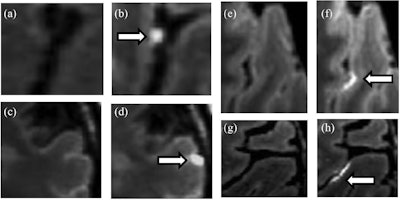

Previous MS studies with 3-tesla MRI have shown that leptomeningeal enhancement occurs in 20% to 50% of patients with progressive MS. Now, with the advent of 7-tesla MRI, researchers have discovered leptomeningeal enhancement in approximately 90% of MS patients. The condition is particularly onerous because it can persist for years and cause an MS patient's disability to progress even further.

To explore the influence of leptomeningeal enhancement in the disease, Zurawski and colleagues enrolled 30 patients (mean age, 44.0 ± 11.3 years) with relapsing-remitting MS and 15 heathy control subjects (mean age, 44.1 ± 10.0 years), all of whom underwent 7-tesla MRI scans (Magnetom Terra, Siemens Healthineers) with a 32-channel receive head coil to detect leptomeningeal enhancement and gray-matter lesions.

As one might expect, 7-tesla MR images revealed leptomeningeal enhancement in 20 MS patients (67%), compared with only one leptomeningeal enhancement (7%) among the healthy controls. The researchers also observed a total of 54 foci of leptomeningeal enhancement among those 20 subjects for a mean of 2.7 (± 1.5; range 1-6) foci per patient.